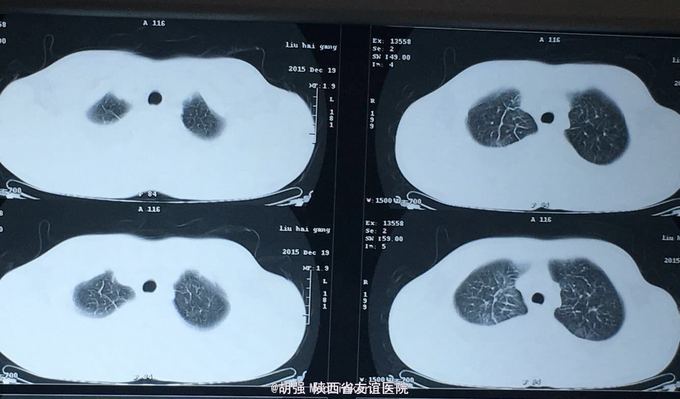

查体:口唇无发绀,咽充血,双侧扁桃体2度大,表面可见脓胎。两肺呼吸音粗糙,可闻及管状呼吸音。余查体无明显异常。 辅助检查:血常规提示白细胞及血小板明显低于正常值,肝功提示转氨酶升高。凝血系列:PT、APTT时间明显延长。T sport试验弱阳性。10月份胸部CT平扫未见明显异常。10月26日及12月12日胸片未见明显异常。12月19日胸部CT提示:两肺斑片状阴影,两侧胸腔积液。